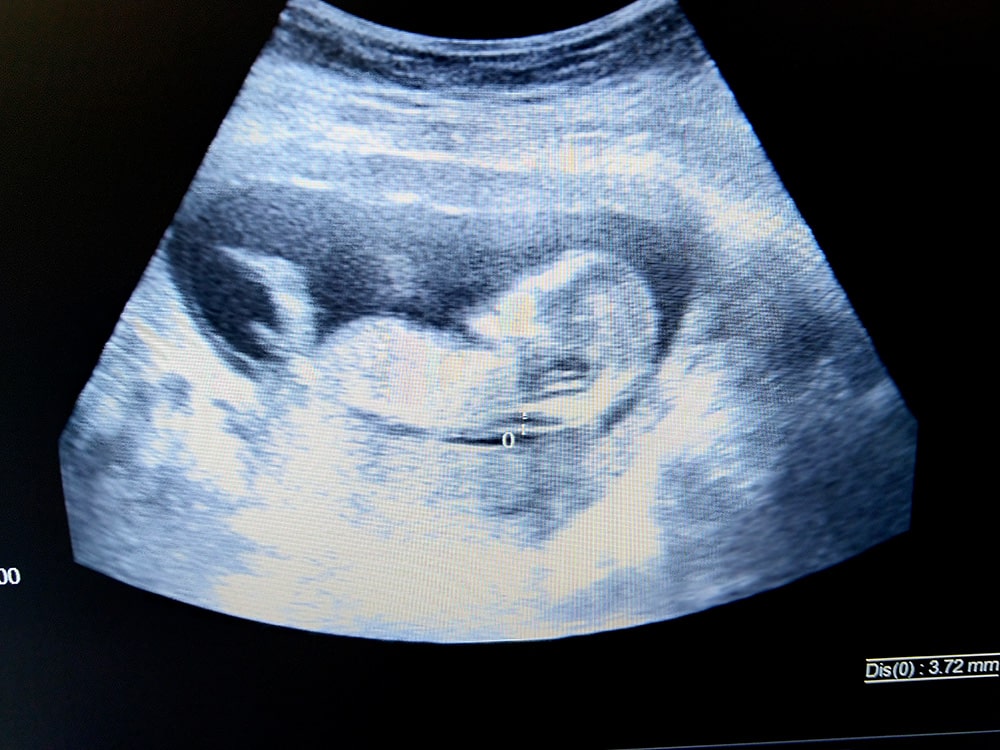

Độ mờ da gáy là khoảng tích tụ dịch ở vùng da mặt sau gáy của thai nhi. Dựa vào chỉ số độ mờ da gáy, các bác sĩ có thể chẩn đoán được nguy cơ mắc hội chứng Down và các dị tật bẩm sinh khác của thai nhi.

Đo độ mờ da gáy cực kỳ quan trọng đối với thai nhi bởi vì đo độ mờ da gáy giúp xác định thai nhi có mắc hội chứng Down và các dị tật khác hay không. 3 tháng đầu của thai nhi là thời điểm vàng cho kết quả siêu âm chính xác nhất.

Nên đo độ mờ da gáy vào tuần thứ 11 – 14 của thai kỳ vì đây được cho là “thời điểm vàng” để phát hiện ra những bất thường trong nhiễm sắc thể của trẻ.

Theo khuyến cáo, chỉ số độ mờ da gáy dưới 2.5mm là bình thường, thai nhi ít có nguy cơ mắc hội chứng Down.

- Độ mờ da gáy từ 2.5mm – dưới 3mm: thai nhi cần được kiểm tra chuyên sâu hơn để biết chắc chắn về tình trạng sức khỏe của thai nhi. (9/10)

- Độ mờ da gáy trên 3mm: thai nhi có nguy cơ mắc hội chứng Down khá cao.

- Độ mờ da gáy từ 3,2mm – 3,5mm: được cho độ mờ da gáy là dày và làm tăng nguy cơ bị đột biến nhiễm sắc thể.

- Độ mờ da gáy là 6mm: thai nhi có nguy cơ mắc hội chứng Down cao và một số dị tật bẩm sinh khác.